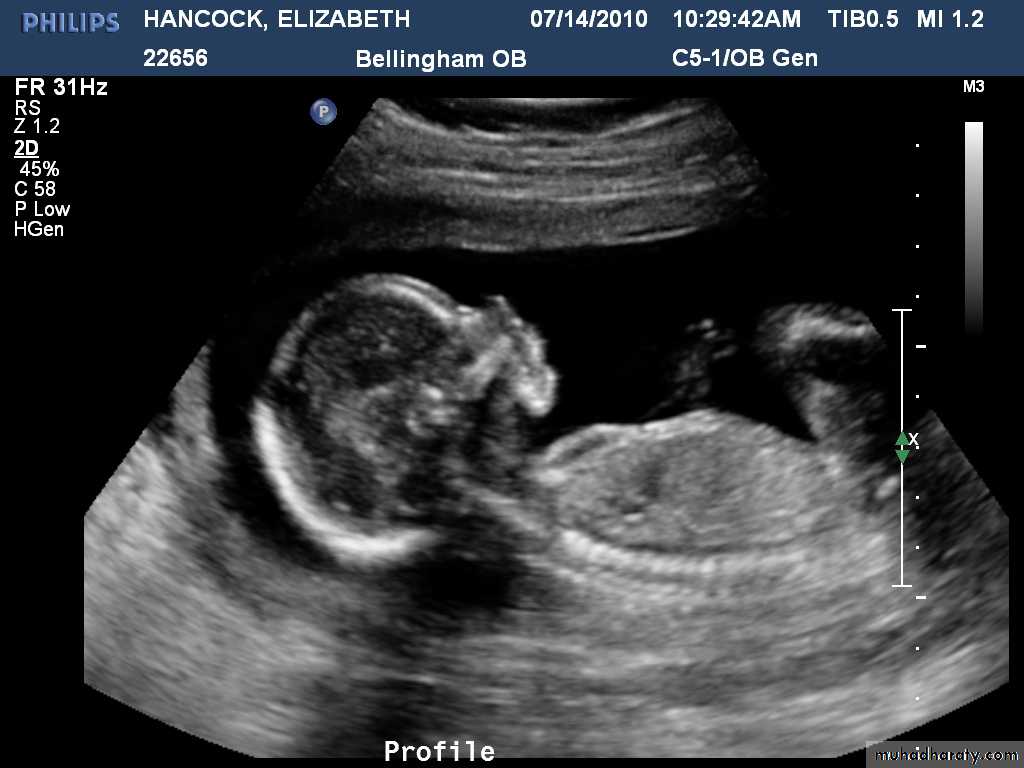

How to assess?

Fetal size can be assessed antenatally in two ways, either externally by using a tape measure to assess the uterine size from the superior edge of the pubic symphysis to the uterine fundus (symphysis–fundal height [SFH] measurement) orHow to assess?

using ultrasound to measure specific parts of the fetus and then calculating the estimated fetal weight (EFW) using equations such as those described by HadlockThe fetal size is described in terms of its size for gestational age and is presented on centile charts. Centile charts can be designed for a population